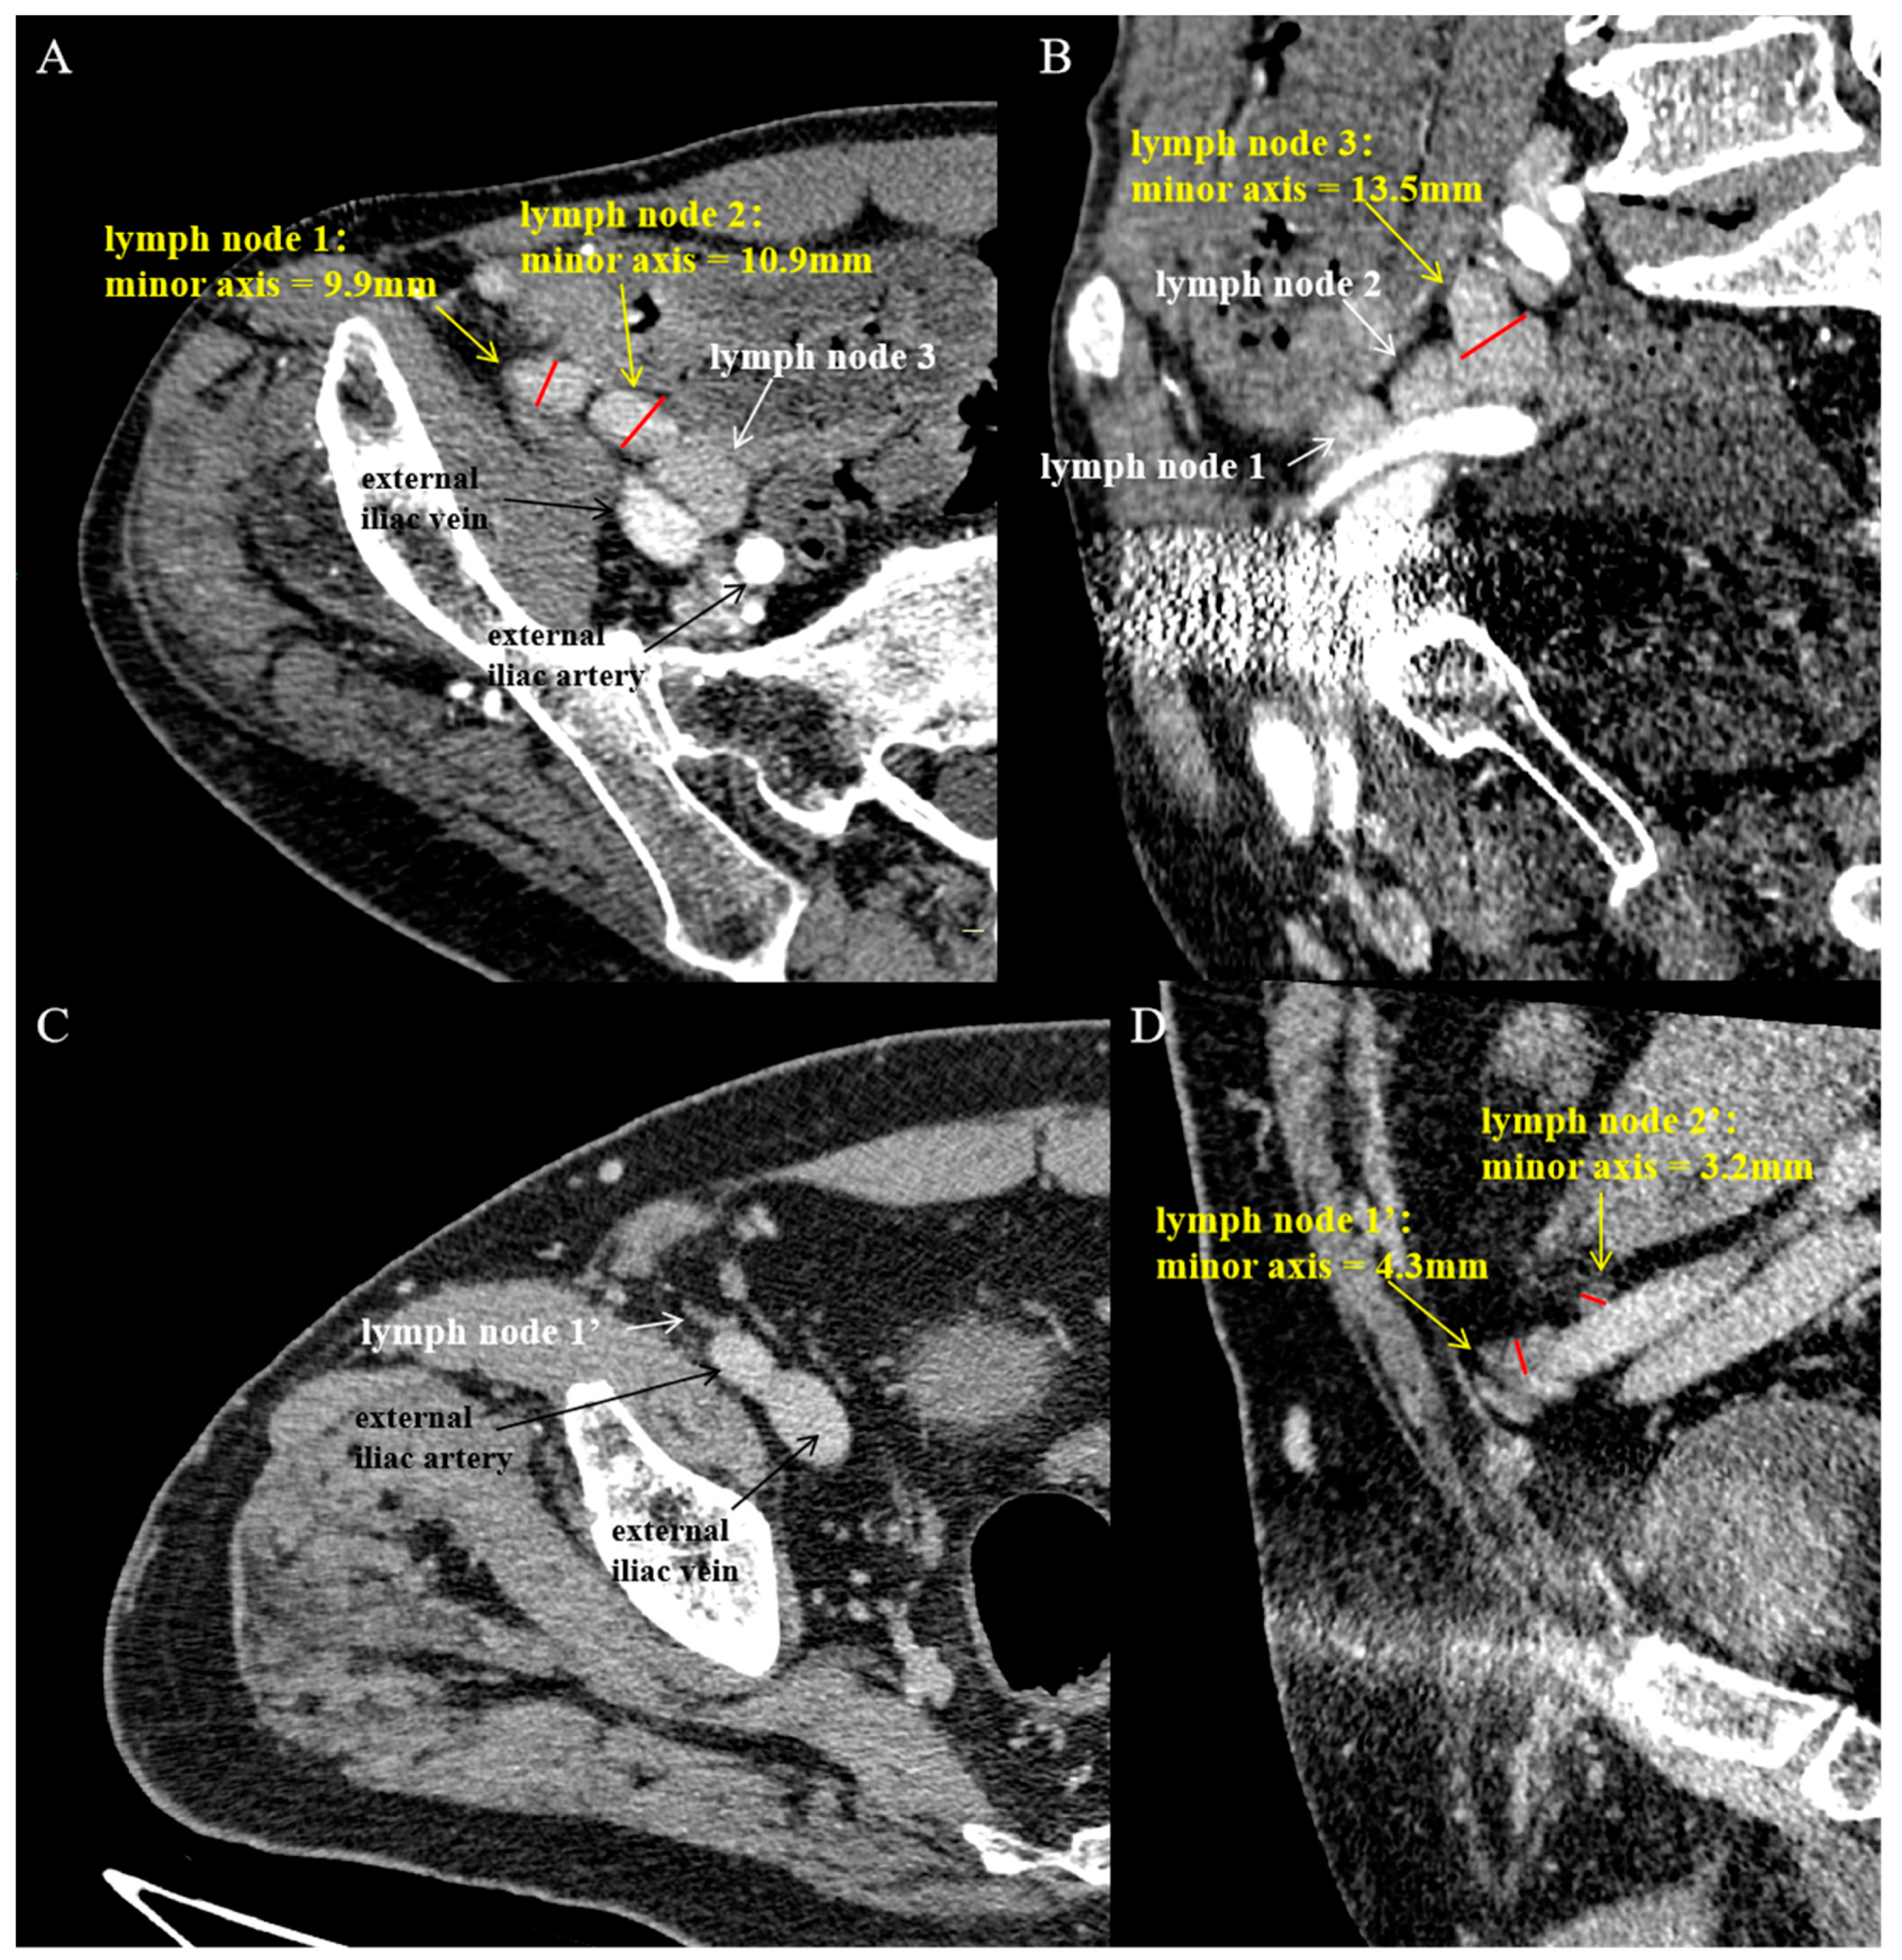

3.3. Counting Enlarged External Iliac Lymph Nodes on DECT

| Lymph node (N) | 4.0 (3.0, 5.0) | 1.5(1.0, 2.0) | <0.001 |

| Enlarged lymph nodes | 0.91 (0.85 to 0.98) | 88.89 (79.58 to 94.26) | 86.84 (72.67 to 94.25) | 2.500 | 80.49 | 94.12 | 88.18 |